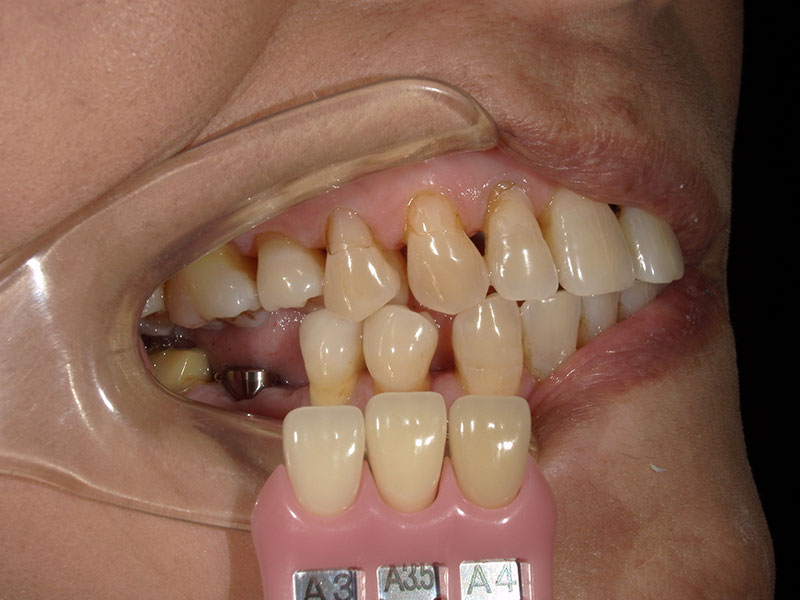

インプラント埋入後におよそ3ヶ月後にインプラント部の型取りとシェード採取を行います。クローズドトレー法という方法で行いました。

インプラント上部構造装着

インプラントの上部構造と言って、インブラントの「歯」に核当する部分を装着しました。隣在歯との歯にも調和しています。患者様にも咬みやすいと喜んでいただくことができました。